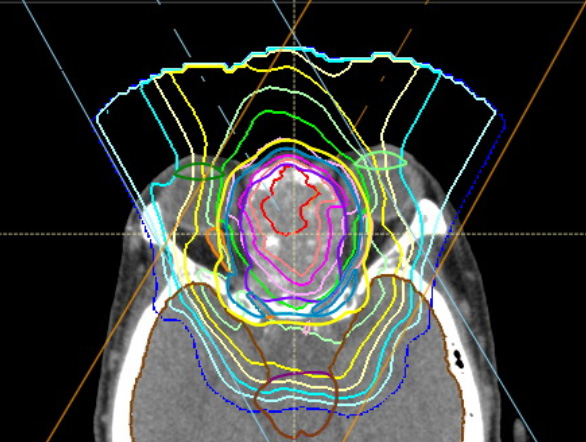

重要な臓器が密集している頭頸部のがんに特に有用と言われているスキャニング照射が使えますので、きめ細かな治療が可能です。

下に篩骨洞がんに対するスキャニング照射の線量分布を示します。眼球・視神経・脳といった重要臓器に囲まれた非常に治療の難しい部位ですが、腫瘍の形に沿った無駄のない照射となっています